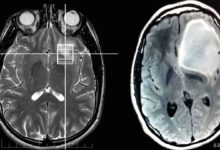

Damak kanseri erken teşhis edilirse tedavi çok başarılıdır. Doktor, kanserin damak dışına yayıldığından şüpheleniliyorsa aşağıdaki görüntüleme prosedürlerini isteyebilir:

• Tümörün vücuttaki yakın dokuları veya diğer organları istila edip etmediğini belirlemek için görüntüleme çalışmaları